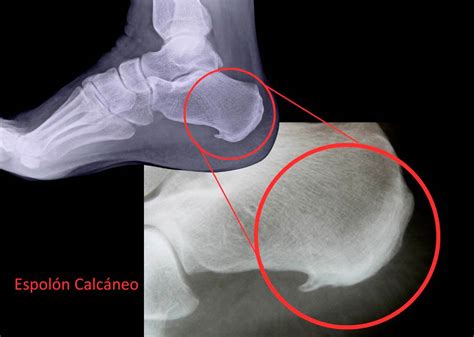

Espolón Calcáneo

¿Alguna vez has sentido dolor al apoyar el talón en el suelo? ¿Un dolor punzante e intenso, como si estuvieras pisando una pequeña piedra o un clavo? El espolón calcáneo, también llamado exóstosis calcánea, es una pequeña calcificación que se forma en el talón, normalmente como consecuencia de una fascitis plantar crónica. Aunque a veces no presenta síntomas, cuando aparece dolor puede resultar muy incapacitante y limitar la actividad diaria o deportiva.

¿Qué es el Espolón Calcáneo?

El espolón calcáneo es una excrecencia ósea puntiaguda que aparece en la parte inferior del calcáneo (el hueso del talón). Esto se debe principalmente a que la fascia plantar, al inflamarse de forma repetida, “tira” del punto donde se inserta en el talón.

El espolón se puede diagnosticar con una radiografía lateral del calcáneo, donde se reconoce una protuberancia orientada hacia los dedos que puede variar entre 1 y 5 mm. Sin embargo, la radiografía no siempre explica por qué duele, ya que hay personas con espolón sin dolor y otras sin espolón que sí lo tienen.

Radiografía de un espolón calcáneo.